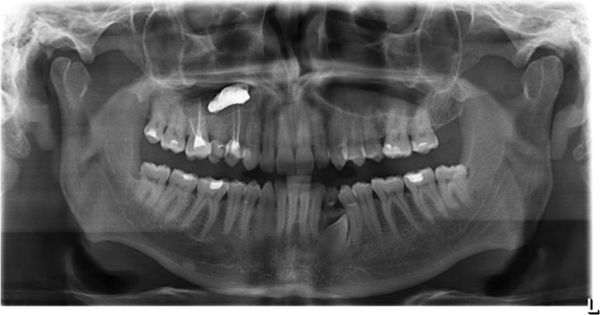

Патогенез мицетомы околоносовой пазухи

В основном мицетома гайморовой пазухи образуется тогда, когда через сообщающийся канал зуба в неё попадает пломбировочный материал. В состав пломбы входят оксид цинка и сульфат бария, образующие пищевую среду для аспергиллов, что провоцирует развитие мицетомы.

![Пломбировочный материал в гайморовой пазухе [15]](/pimg3/luchevaya-diagnostika-mitsetomi-60767.jpeg)

Отдельной причиной можно выделить некачественное стоматологическое лечение, в результате которого происходит попадание инородных тел в пазуху — пломбировочного материала, обломков инструментов. Такое возможно при анатомически близком расположении верхних жевательных зубов к носовому синусу, а у некоторых людей корни и вовсе находятся в пазухе, отделяются только слизистой оболочкой.

Без предварительной диагностики, не учитывая локализацию корней, стоматолог может не рассчитать усилия, проткнуть верхушку корня инструментом и протолкнуть пломбировочный материал в пазуху. Соли цинка в составе материала играют роль катализатора, запускают механизм образования мицетомы, особенно под влиянием общих факторов, ослабляющих защитные функции организма. Ускорить разрастание грибковой колонии может обломок инструмента в канале, выведенный за пределы верхушки корня в просвет пазухи. Такое случается при проведении лечения неопытным врачом без предварительной диагностики.

Компьютерная диагностика перед лечением жевательных зубов верхней челюсти — обязательное условие. 3D-снимки позволяют оценить расположение корней и спланировать безопасную тактику лечения. В нашем Центре КТ проводится на высокоточном компьютерном томографе Sirona с настройками ЛОР-режима, позволяющими оценить состояние пазухи, локализацию зубных корней по отношению к ней.